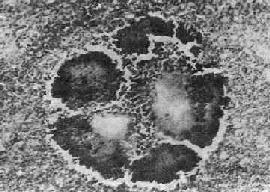

放线菌病和病变为慢性化脓性炎症。局部组织水肿,有大量中性粒细胞和单核细胞浸润,其间逐渐出现许多大小不等的坏死区,形成多数小脓肿,周围纤维组织增生。脓肿大小不等,常相互融合,并向邻近组织蔓延,形成许多窦道和瘘管。脓肿壁和窦道周围肉芽组织内有大量中性粒细胞、淋巴细胞和单核细胞浸润,有时并有少数多核巨细胞,部分可见大量吞噬脂类的巨噬细胞,因此肉眼观常带黄色。放线菌在脓肿壁、窦道壁和脓腔内繁殖,形成菌落。有时肉眼可见脓液内有细小的黄色颗粒,直径约1~2mm,称为“硫黄颗粒”。取硫黄颗粒直接压片或在组织切片中可见颗粒由分支的菌丝交织而成。在HE染色的组织切片中,颗粒中央部分染蓝紫色,周围部分菌丝排列成放线状,菌丝末端常有胶样物质组成的鞘包围而膨大呈棒状,染伊红色,所以称为放线菌(图18-36)。

图18-36 放线菌病

病灶中的“硫黄颗粒”,周围部分菌丝排列成放线状。菌丝末端膨大呈棒状